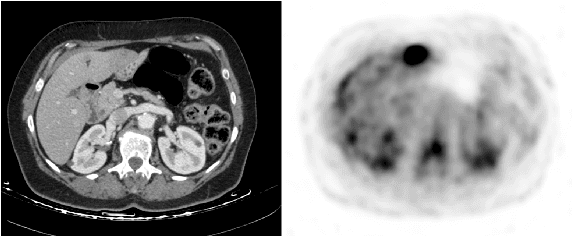

Abstract:In this work we present a novel system for generation of virtual PET images using CT scans. We combine a fully convolutional network (FCN) with a conditional generative adversarial network (GAN) to generate simulated PET data from given input CT data. The synthesized PET can be used for false-positive reduction in lesion detection solutions. Clinically, such solutions may enable lesion detection and drug treatment evaluation in a CT-only environment, thus reducing the need for the more expensive and radioactive PET/CT scan. Our dataset includes 60 PET/CT scans from Sheba Medical center. We used 23 scans for training and 37 for testing. Different schemes to achieve the synthesized output were qualitatively compared. Quantitative evaluation was conducted using an existing lesion detection software, combining the synthesized PET as a false positive reduction layer for the detection of malignant lesions in the liver. Current results look promising showing a 28% reduction in the average false positive per case from 2.9 to 2.1. The suggested solution is comprehensive and can be expanded to additional body organs, and different modalities.